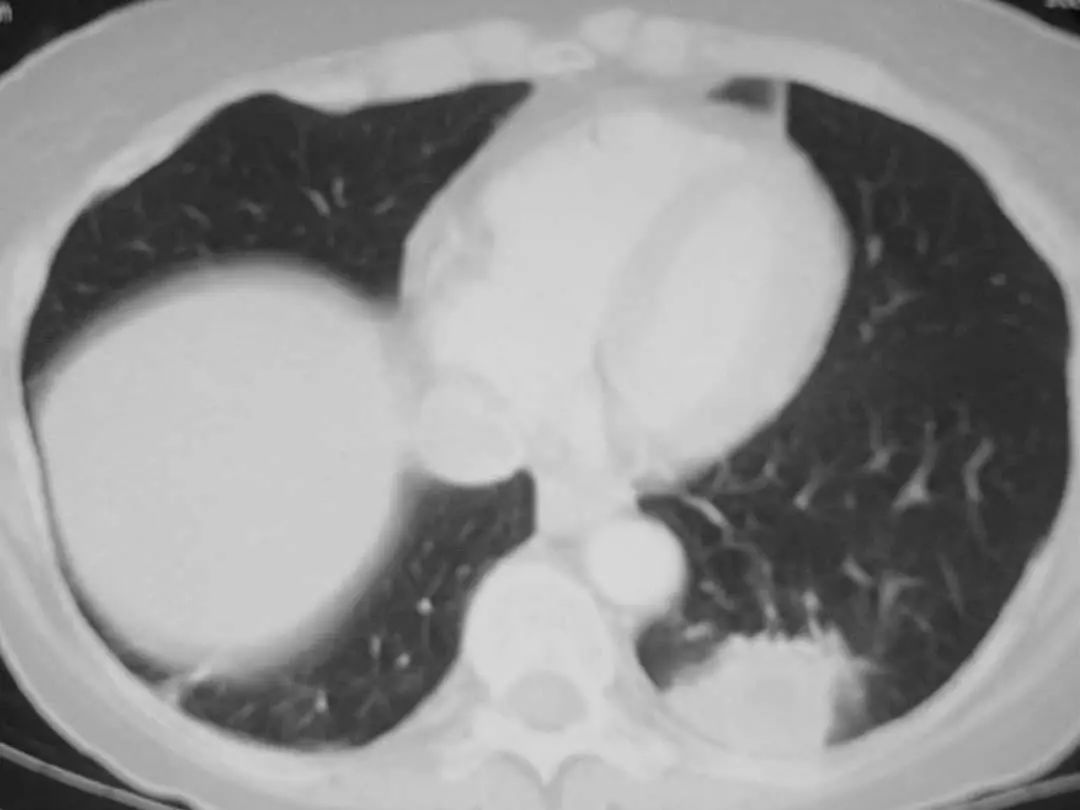

图1.11 49岁的肺炎球菌性肺炎患者, 胸部CT显示左上叶不透明延伸至外周。

图1.12 50岁流感嗜血杆菌肺炎患者胸部CT。显示左下叶胸膜附近有致密圆形实变。